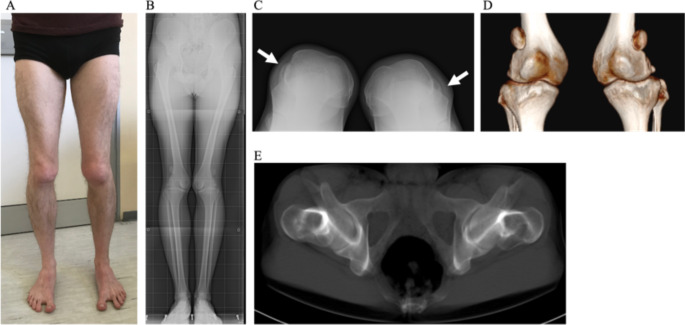

背景:先天性膝关节畸形是一种罕见疾病,其临床和遗传变异性很大,这主要是由于膝关节发育过程复杂。尽管在了解病理机制和相关基因方面取得了进展,但许多患者仍未得到诊断:揭示影响多个家庭成员且严重程度不一的先天性髌骨脱位的遗传基础:方法:我们对表现为双侧髌骨脱位的原发性髌骨脱位患者及其父亲、病情较轻的类似情况的姐姐以及未受影响的母亲进行了 ES 测序。然后,我们又对该患者的兄弟和姑姑进行了 Sanger 测序,他们也都受到了影响:ES 和 Sanger 测序结果表明,所有患病家庭成员的 TBX4 基因中都存在 c.735delT 的新型杂合换框突变。TBX4与常染色体显性的伴/不伴肺动脉高压(ICPPS,#147891)的等位-缺氧-足趾-髌骨综合征有关,并在该家族中得到确诊。家族内的临床异质性表明,可能还与其他因素有关,如 TBX4 或其他修饰基因的额外变异。有趣的是,我们只在表型更为严重的原告身上发现了 TBX4 基因的三个额外变异。尽管这些变异被归类为良性变异,但其中一个变异预计会破坏剪接蛋白的结合位点,因此可能会影响 TBX4 的替代剪接,从而导致该患者的表型更为严重:我们扩展并进一步划分了ICPPS的基因型和表型谱。结论:我们扩展并进一步划分了ICPPS的基因型和表型谱,有必要进一步研究该变异的潜在影响以及TBX4相关表型的不同表现。

Methods: We performed ES in the proband and his father, both showing bilateral patellar dislocation, his sister with a milder similar condition, and his unaffected mother. Sanger sequencing was then performed in the proband's brother and paternal aunt, both affected as well.

Results: ES and Sanger sequencing identified the presence of the novel heterozygous frameshift mutation c.735delT in the TBX4 gene in all affected family members. TBX4 is associated with autosomal dominant ischio-coxo-podo-patellar syndrome with/without pulmonary arterial hypertension (ICPPS, #147891), reaching a diagnosis in the family. Intrafamilial clinical heterogeneity suggests that other factors might be involved, such as additional variants in TBX4 or in other modifier genes. Interestingly, we identified three additional variants in the TBX4 gene in the proband only, whose phenotype is more severe. Despite being classified as benign, one of these variants is predicted to disrupt a splicing protein binding site, and may therefore affect TBX4 alternative splicing, accounting for the more severe phenotype of the proband.